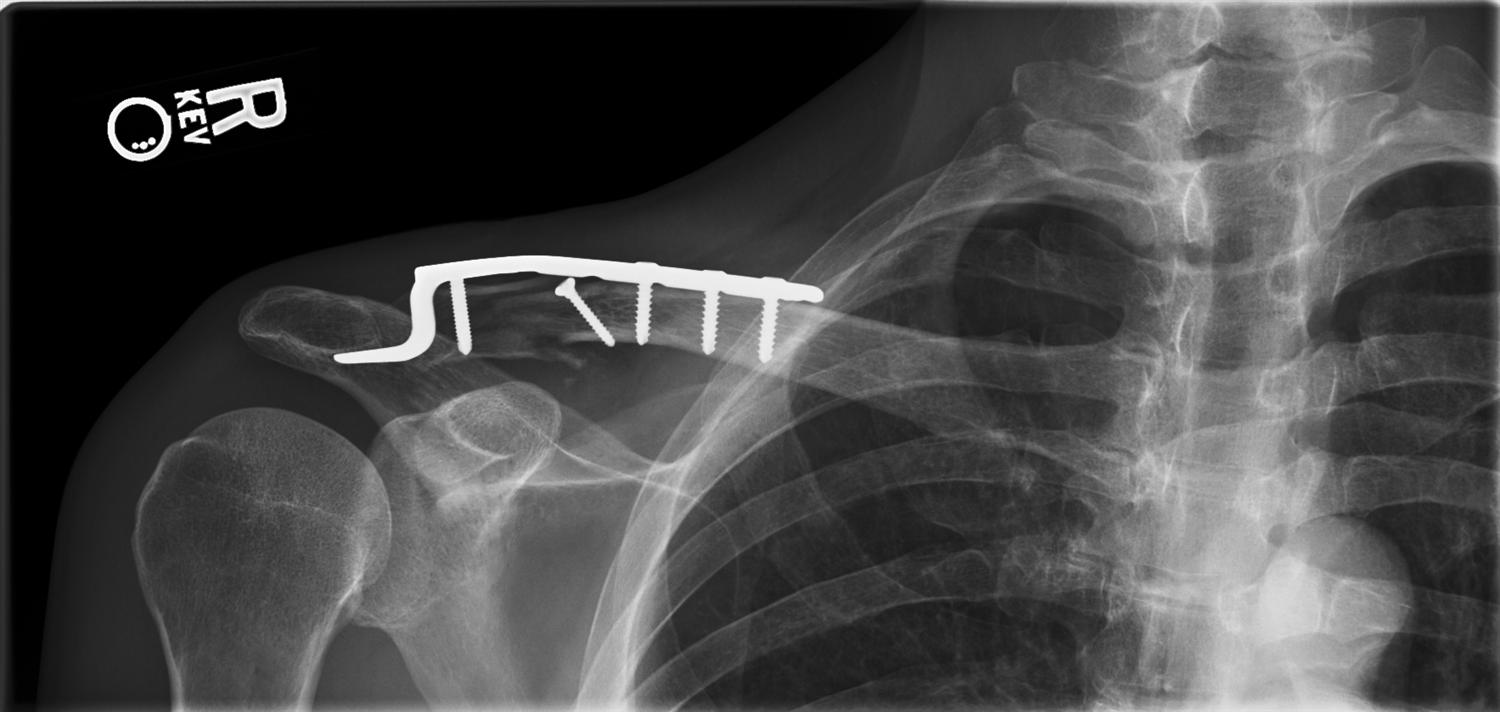

Clavicle Fracture Open Reduction and Internal Fixation Johns Hopkins Treatment Fracture Of The Clavicle what is the treatment for a clavicle fracture? treatment of clavicle fractures. treatment for a broken collarbone. Only a small percentage will need surgery. most clavicle fractures heal well with conservative treatment. A broken collarbone needs to be. For the vast majority of clavicle fractures that are not out of place, or only minimally out of. Treatment Fracture Of The Clavicle.

Surgery for Clavicle Fracture (Broken Collarbone) Treatment Fracture Of The Clavicle most clavicle fractures can be treated without surgery. many clavicle fractures can be treated by wearing a sling to keep the arm and shoulder from moving while the bone heals. You may also need to include chest and scapula. Only a small percentage will need surgery. treatment for a broken collarbone. most clavicle fractures heal well. Treatment Fracture Of The Clavicle.